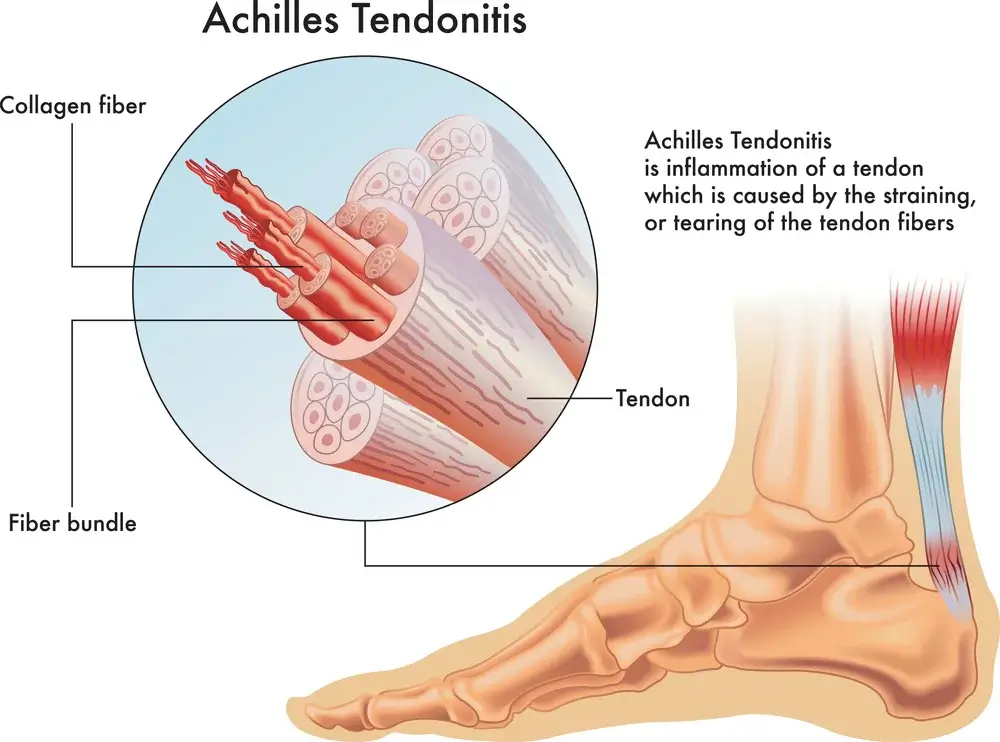

Tendonitis:

Tendonitis is a common problem that can be caused by a number of different factors. Musculoskeletal diseases, such as rheumatoid arthritis (RA) and chronic pain, are the most common causes of tendonitis. Other causes of tendonitis include overuse, trauma, and genetics.

Tendonitis rheumatologic and musculoskeletal (TRAM) is a common inflammatory condition that can affect any tendon, joint or muscle in the body. TRAM is most commonly caused by rheumatic diseases such as rheumatoid arthritis (RA), juvenile idiopathic arthritis (JIA) and ankylosing spondylitis (AS).